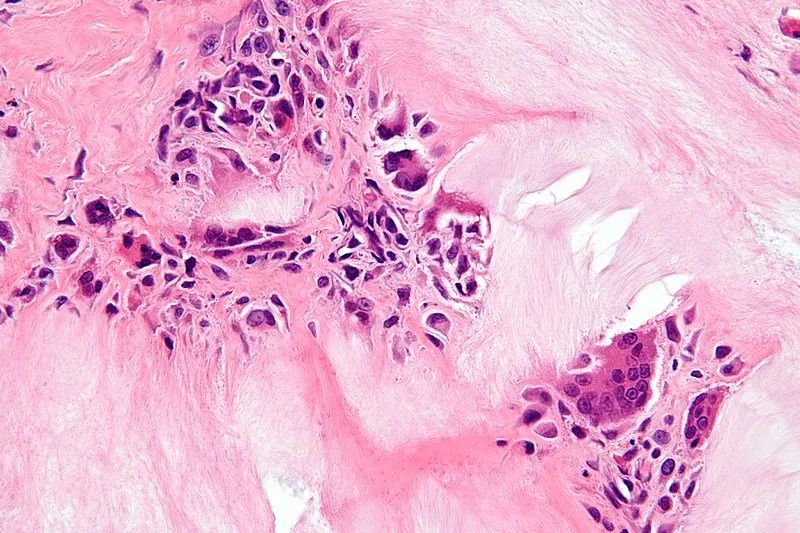

痛风石长这样 图/Wikimedia

引用自 https://commons.wikimedia.org/wiki

/File:Gouty_tophus_-_very_high_mag.jpg

痛风石通常出现在哪儿?一般在耳廓、关节周围、肌腱、软组织等周围皮下可见。